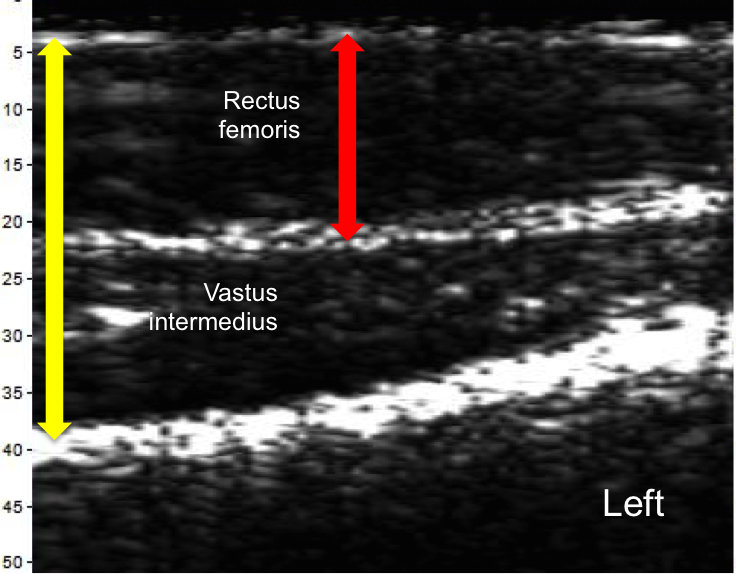

The scans below taken of the left and right quadricep from the midpoint to near the patella were recorded on the same day. The scans show clear differences. The yellow and red arrows represent the same thickness in each image, showing significant imbalance. The ratio of the Rectus Femoris thickness to the Vastus intermedius is 1.3 for the left leg and 0.8 for the right leg.